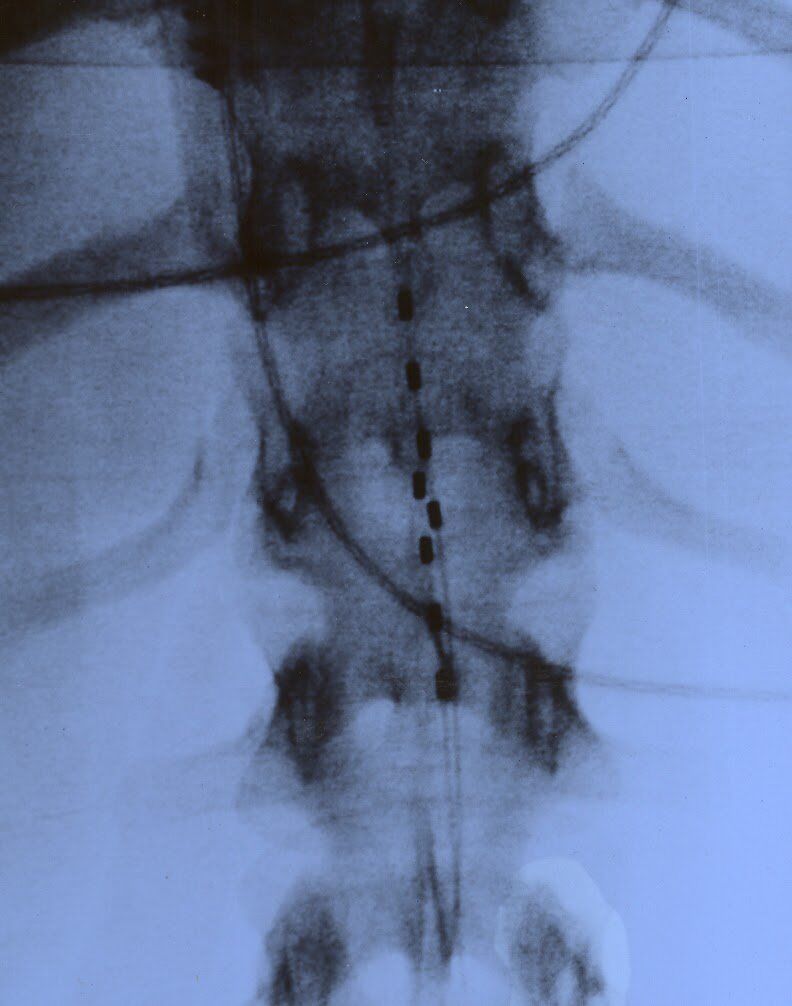

During the implant, a local anesthetic is injected to numb the low back. Using X-ray fluoroscopy, a hollow needle is inserted subcutaneously into the epidural space between the bone and spinal cord. The doctor will insert a single trial lead and position it within a specific region near the spinal cord. The wires will connect to an external generator worn on a belt.

The patient will be sent home and instructed to monitor and care for the incision. Doctors will request the patient to keep a written log of the stimulation settings during different activities and note the level of pain relief. After a trial period spanning between 4 to 7 days, the patient will return to the medical center to finalize with the attending doctor if a permanent form of SCS will be needed. If the trial is successful, a second surgery will be scheduled, which by then will involve a full set of SCS leads that will cover the entire pain area identified for treatment. The surgery typically takes about an hour..